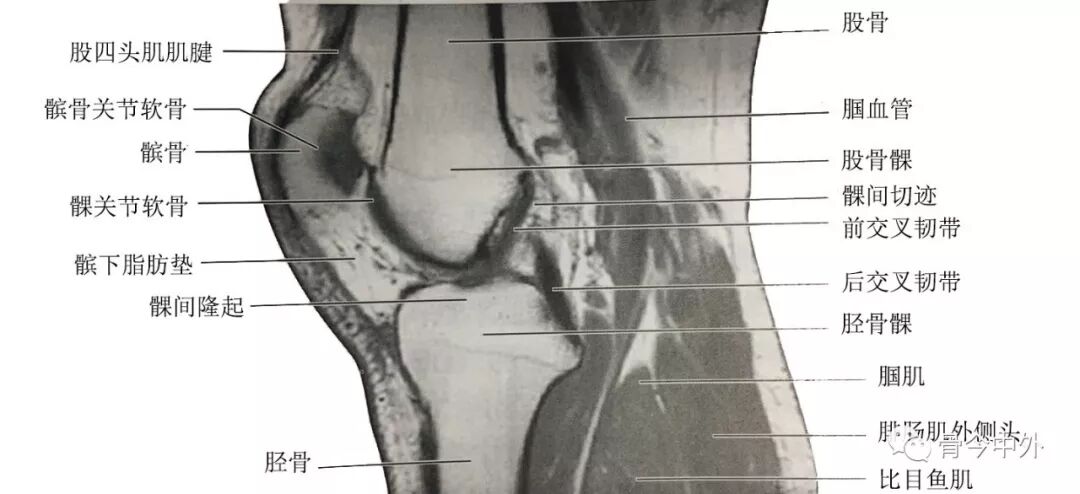

(2)膝正中矢状断层:该层面解剖关系结构如图

膝正中矢状断层